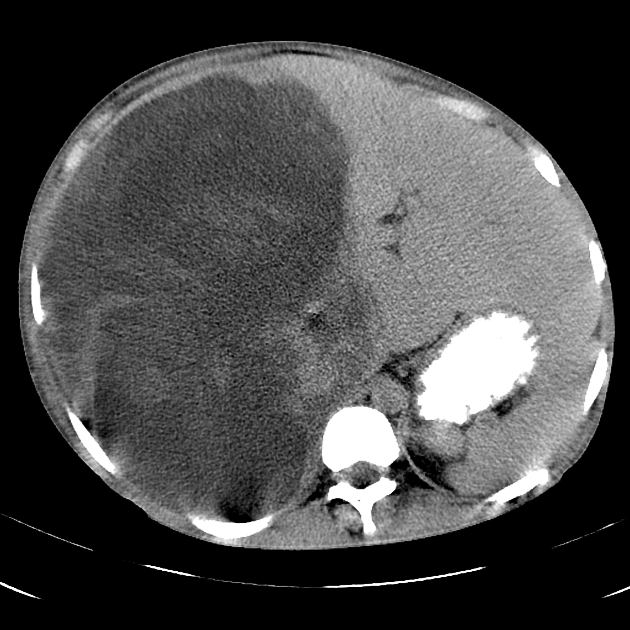

Hepatoblastoma

MC primary malignant liver tumor in peds <4

^ AFP and painless abd mass

Most sporadic but can be a/w BW, hemihypertrophy